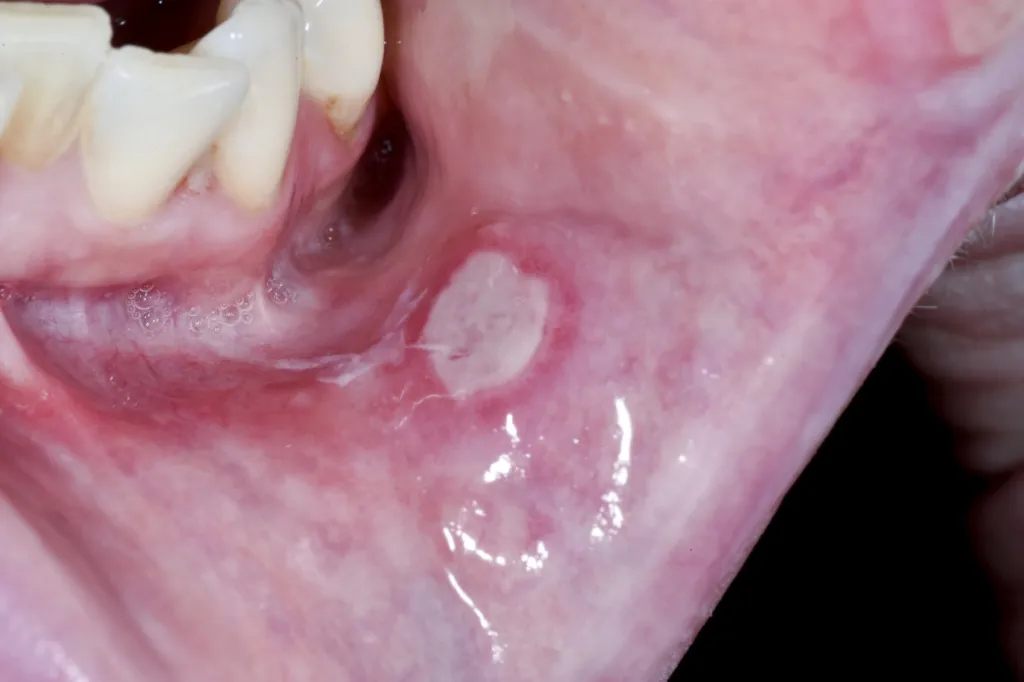

Herpangina is a viral infection caused by a group of common viruses called enteroviruses. It causes small blister-like bumps or ulcers to form on the throat and roof of the mouth.

- Mouth sores — Grayish blister-like sores appear on the mouth and throat 1 to 2 days after the sore throat begins. They develop into shallow mouth ulcers over the next 24 hours and are usually smaller than 5 mm in diameter.

Tests usually aren’t necessary because the sores that develop are unique to herpangina. A physical exam is typically all your doctor needs to confirm the diagnosis.

- Sores caused by a herpangina infection — Only affect the throat, tonsils, uvula, tongue, roof of the mouth, and soft palate.